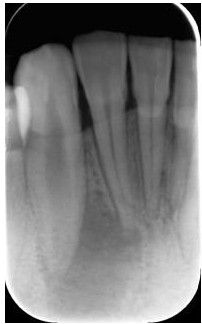

一、术前拍摄X线片评估牙齿冠、根情况以及牙槽骨情况

在根管治疗过程中,在根管治疗术前拍X线片,以帮助诊断,了解髓室的位置和根管数目及形态,测量根管工作长度及日后随访和评价疗效提供对比的依据。